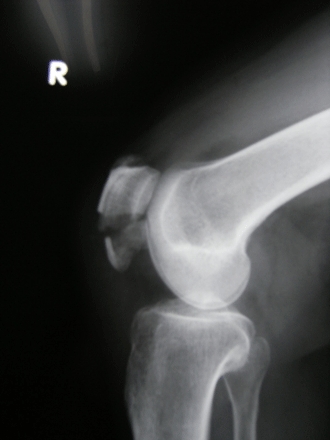

DSCF1044.gif膝の皿が横に割れている(半月板骨折)「手術です」といわれる〜

DSCF1065.gif急遽明日、沖縄へ戻って手術をすることに…